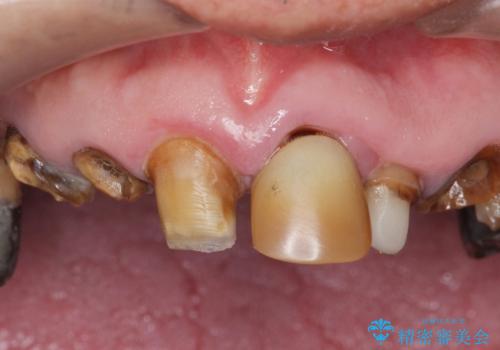

- 前歯の被せ物がとれたまま放置されていた患者様です。

前歯4本のうち3本の被せ物が脱離し、残りの1本の被せ物は劣化し変色していました。

古い被せ物や土台・虫歯をしっかり除去したのち、セラミック治療を行いました。

患者様のご希望により、根尖病変の明らかな左上2のみ根管治療を行いました。